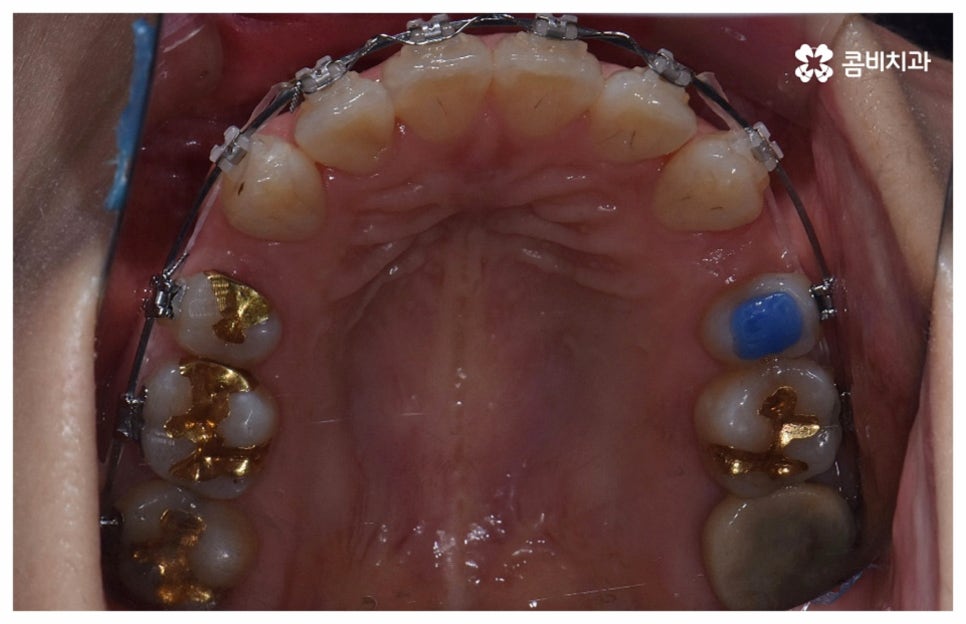

위 사진은 환자분의 동의를 받아 이해를 돕기 위한

사진이며, 실제 치료 결과는 다를 수 있습니다.